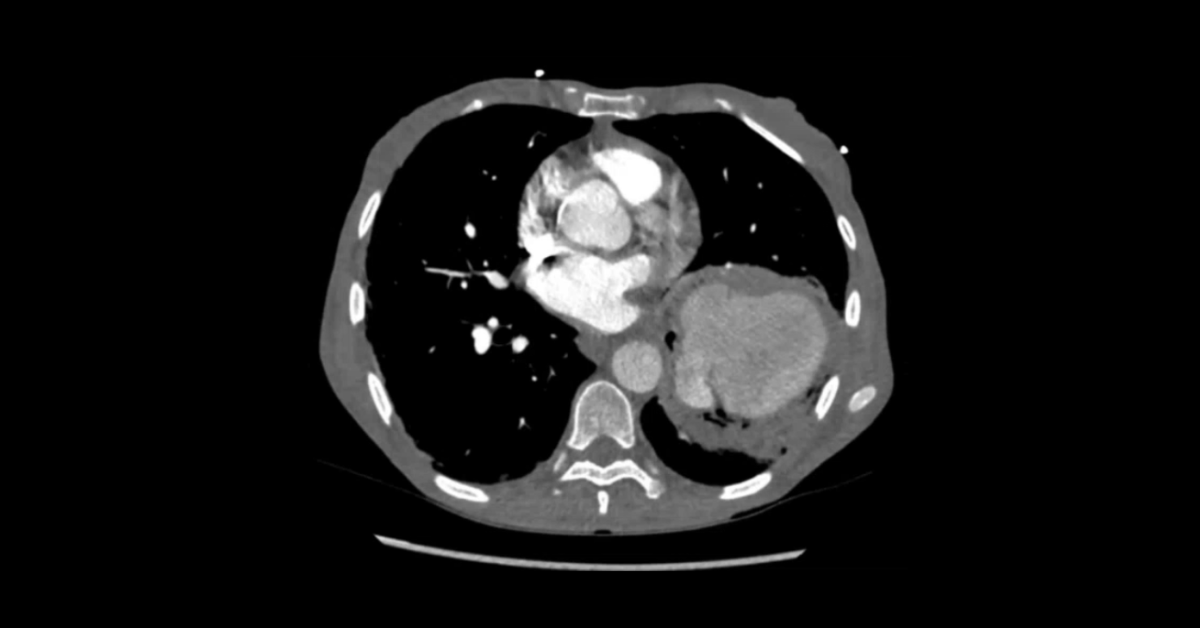

Presented by Vincent Mellnick, MD at Practical Radiology 2025. This talk will focus complications following the most common bariatric surgeries in my practice: Gastric sleeve, gastric band, and Roux-en-Y gastric bypass. The commonly encountered complications include perforation, hemorrhage, and obstruction. Knowledge of the surgical techniques and complications in both the perioperative period and long-term is crucial for radiologists.